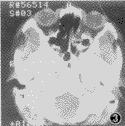

, 百拇医药 6例眼球凹陷及复视均消失,睑裂及眼位与健侧对称。眼球运动良好,术后1个月鼻内窥镜检查:术腔上皮化良好。中鼻道宽畅,骨折处纸板小范围轻度向筛窦内膨隆,CT检查见纸板复位良好(图3,4)。全部病例经0.5~2年随访眼球凹陷均稳定在2 mm以内,无并发症发生。

图3,4 同一患者术后1个月CT(水平位)示眶容复纳及纸板复位良好。